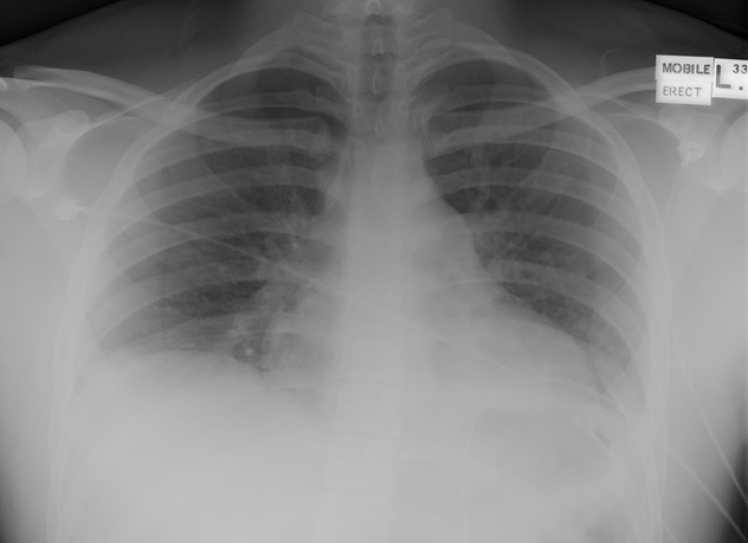

Given the sudden onset of symptoms in this case as well as the age of the patient Pneumothorax was thought to be the most likely diagnosis in the first instance. However, the Chest X-ray (shown below) did not show a Pneumothorax.

The subtle triangular shaped area of opacification seen on the lateral x-ray (at the lung base) was thought to have reflected a diagnosis of early Pneumonia and he was treated for this as a result…

- In the meantime his x-ray (shown below) was repeated.

- The patient is appearing clinically worse despite antibiotics – his repeat X-ray (above) is concerning to the treating team. Could this be a pulmonary infarction associated with PE?